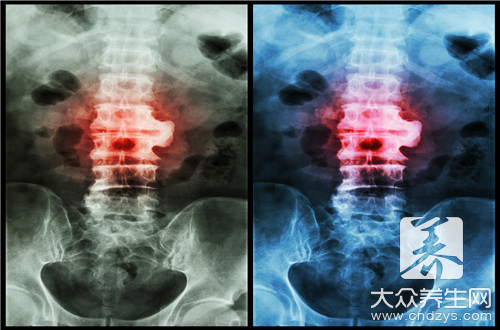

大家都了解,脊柱自身就是说身体的一个支撑点的一部分,其必要性不容忽视。实际上造成脊椎疼痛的原因是比较多的衣食住行之中应当把握这种要素,那样才可以更强的搞好防范措施那麼脊椎疼都是啥原因造成的呢?一起来看一下造成脊椎疼痛的原因吧。

脊柱丰富性疼痛就是指脊柱及两侧疼痛,疼痛范畴范围广,无固定不动压疼点。疼痛可亚急性发病,也可以迟缓产生。亚急性疼痛时,十分强烈,短时间无法忍受,慢性疼痛可持续很长期,各种各样医治常不可以见效。更年期妇女患病率较高,显而易见与骨质疏松相关。颈椎病造成的

(1)颈椎骨第四、五、六颈椎骨的脊神经后支向背部拓宽,操纵上背部的皮肤肌肉。(2)当颈椎骨产生退行性变改变时,假如伸展到第四、五、六颈椎骨的脊神经后支,马上会造成出現背疼。

颈背疼痛、上肢乏力、手指麻木,头昏、恶心想吐乃至视物模糊,咽下模糊不清全是颈椎病的症状表现。